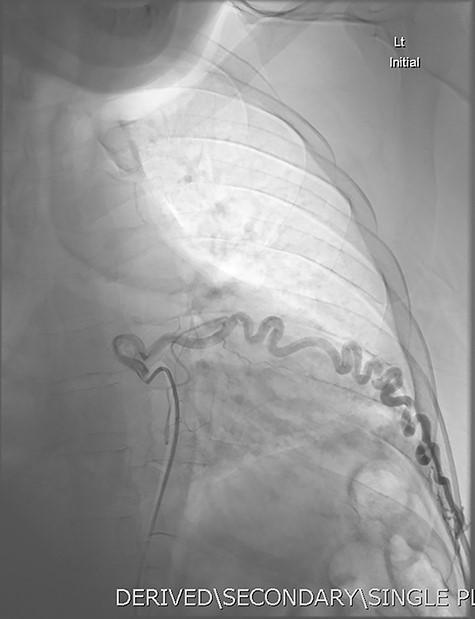

Given the findings, he was referred to Interventional Radiology for a formal digital subtraction angiogram with view of transcatheter embolization. Under local anaesthetic and sedation, a 5-french sheath was placed in the left common femoral artery. Using a 5-french pigtail catheter, aortic angiography was undertaken, confirming the CTPA findings and demonstrating predominant supply of the vascular malformation via the left intercostal arteries and the left inferior phrenic artery (Fig. 4)—draining into the left inferior pulmonary artery and vein. Superselective catheterization of the left intercostal arteries (Fig. 5) and the left inferior phrenic artery (Fig. 6) are shown. Unfortunately, due to the malformation’s volume and complexity, embolization was abandoned. He was subsequently referred to Cardiothoracic Surgery, currently awaiting consideration and workup for ligation and resection via video-assisted thoracoscopy, and potentially thoracotomy.

DSA utilizing superselective catheterization to demonstrate contribution to the PAVM via one of the many tortuous intercostal arteries.